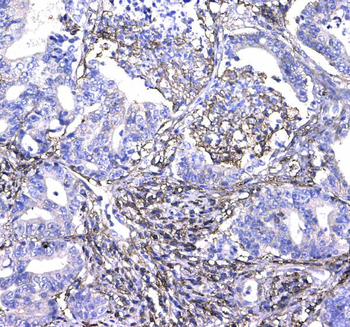

10 μg, 100 μg - Anti-HSD11B2 Antibody [orb316541]

IF, IHC, IHC-Fr, WB

Human, Mouse, Rat

Rabbit

Polyclonal

Unconjugated

10 μg, 100 μg - Anti-CD44 Antibody [orb402179]